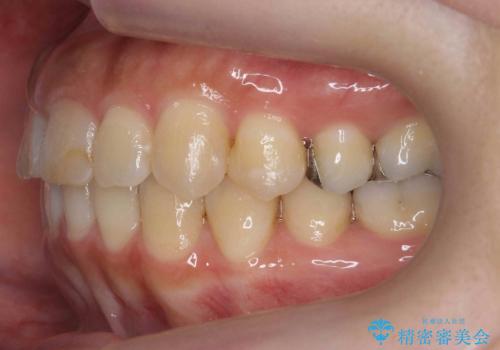

前歯のがたつき ガミースマイルの改善

- 前歯のがたつきとガミースマイルの改善を希望して来院。

ガミーは非常に軽度でひどくはなかったのですが、改善を強く希望されていました。

上の前歯をひっぱりあげて目立たなくするために、上の前歯のワイヤー部分矯正を行い、ミニスクリューからわずかに引っ張り上げました。

また、右上の犬歯の反対咬合についてもワイヤー矯正で短期間で改善することができました。

前歯の過蓋咬合についても改善しています。